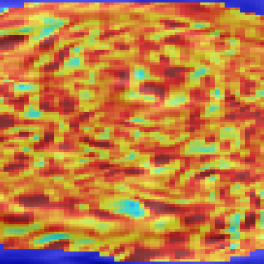

Structural dissimilarity (DSSIM) heat maps are calculated in order to visualize the dissimilarities between original and reconstructed images. DSSIM is calculated as a distance metric derived from SSIM:

| (12) |

The evaluation of the reconstruction quality of a whole 3D image into a single-valued metric may not properly reflect the performance differences, as it is based on averaging values of all the pixels of all the input stacks. Furthermore, Tab. I indicates significant differences between variants of PVR but these differences have only minimal qualitative effect on reconstruction accuracy. Therefore, Fig. 12 evaluates the reconstruction quality of PVR additionally using dissimilarity heat maps based on the measured DSSIM (see Sec. IV-A). This approach allows further qualitative evaluation and allows for uncertainty visualization of PVR reconstructions.